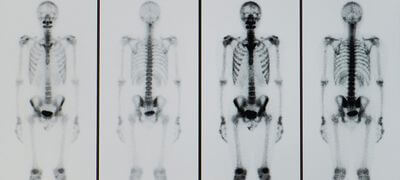

Пухлини кісток

КТ може виявити пухлини кісток, створюючи детальні зображення кісток. Зображення з високою роздільною здатністю, отримані за допомогою КТ, можуть допомогти лікарям визначити місце розташування, розмір і форму пухлини.